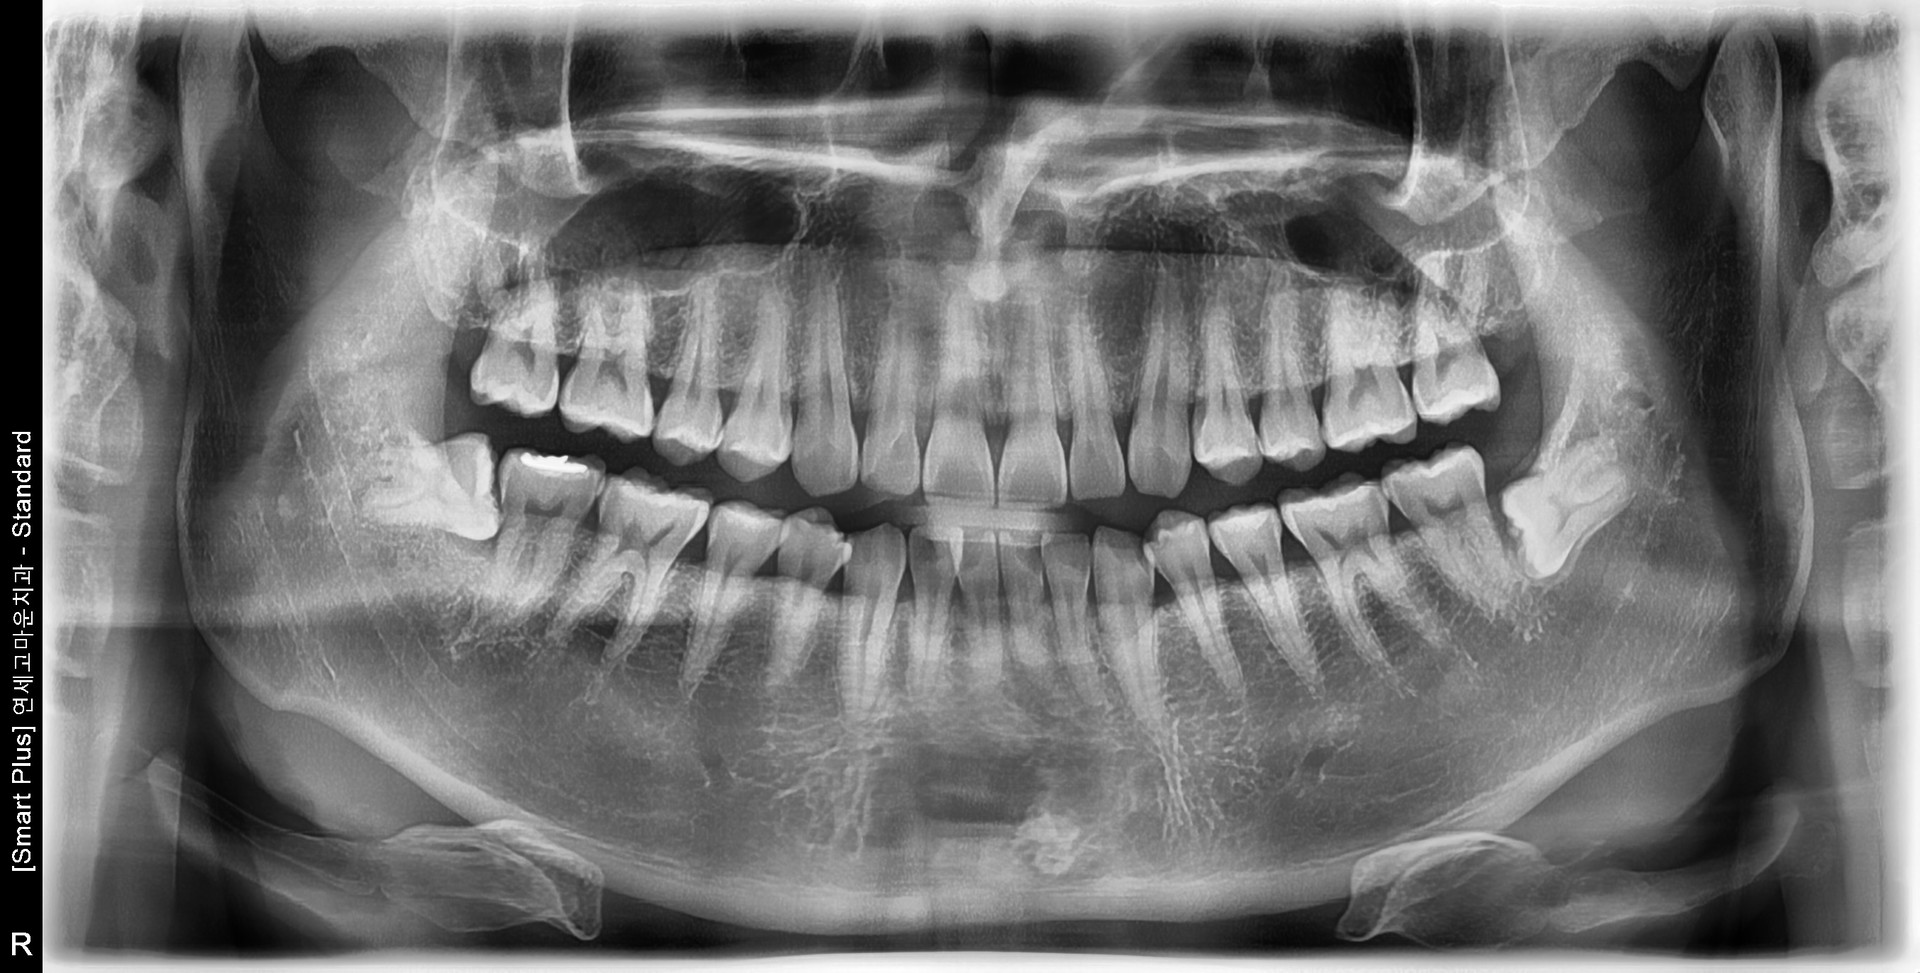

사랑니 발치